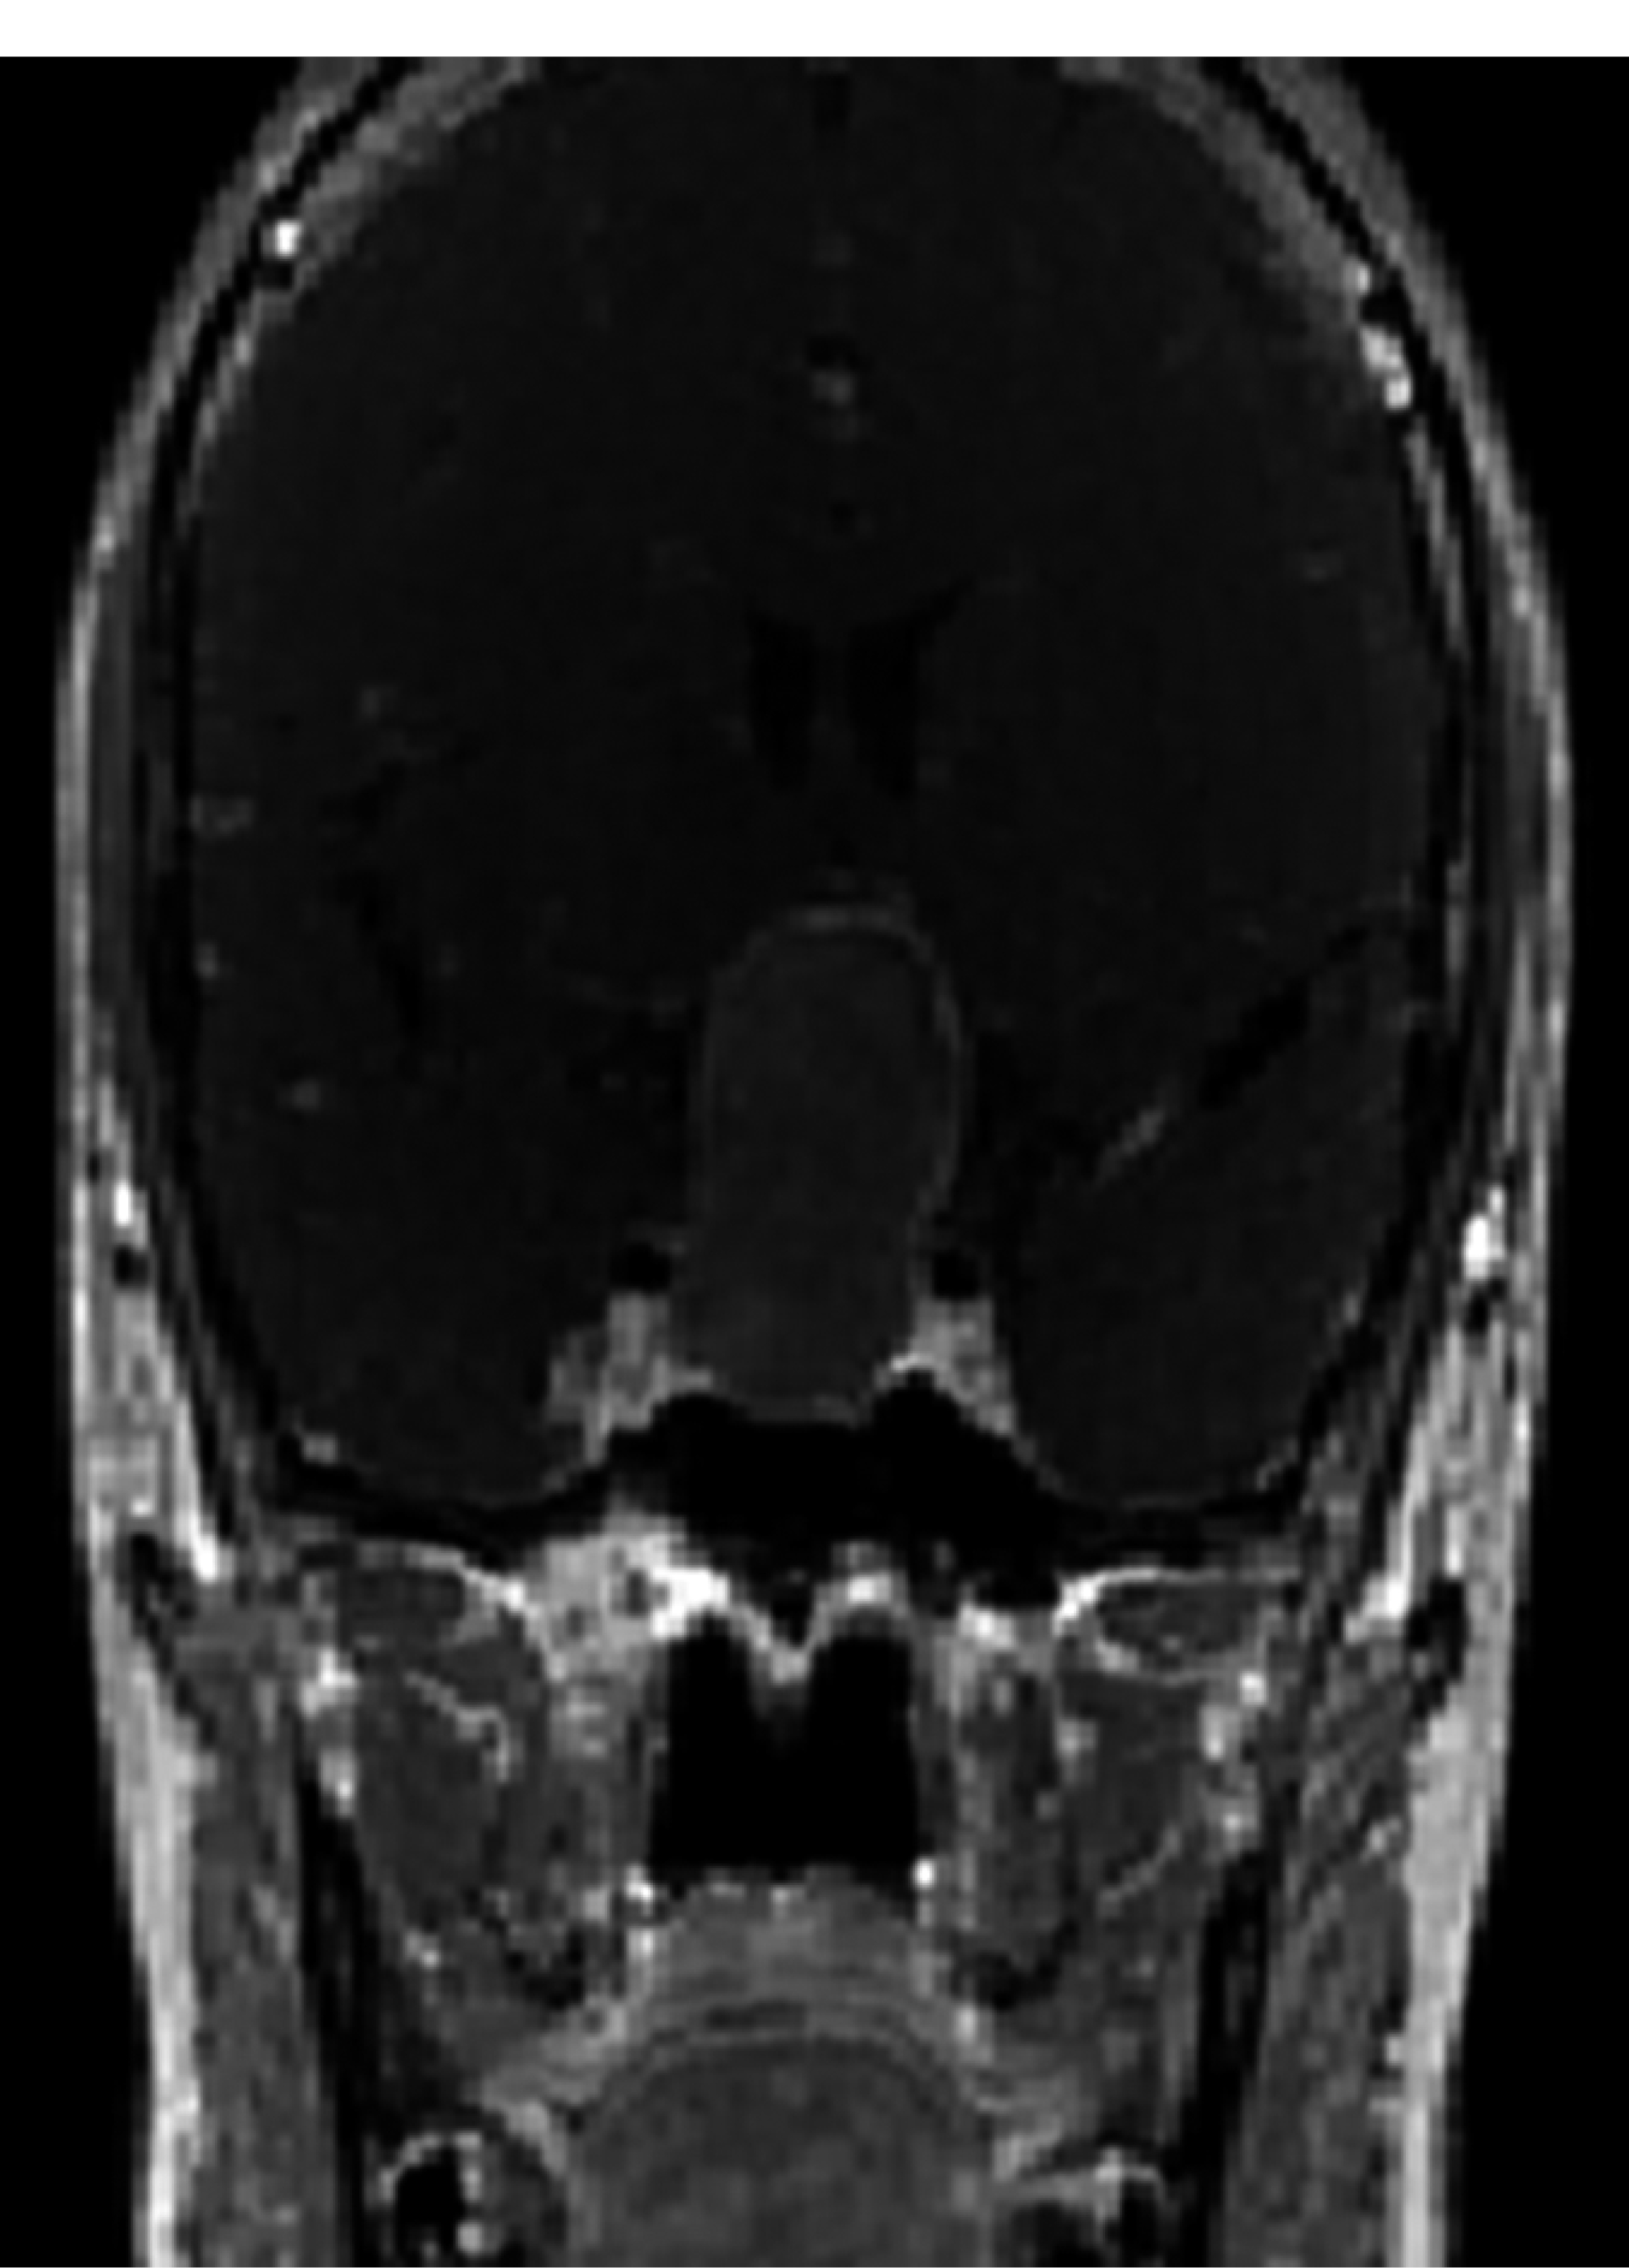

Se trata de mujer de 45 años que inició padecimiento en el 2018 con presencia de cefalea, fue tratada con analgésicos y hemianopsia bitemporal de predominio izquierdo, por lo que acudió a realizarse tomografía axial computarizada (TAC) simple y contrastada de cráneo, en donde se identificó lesión selar. Continuó con protocolo diagnóstico con imagen por resonancia magnética (IRM) de cráneo y se encontró lesión selar (Figura 5). Se inició protocolo preoperatorio solicitando los siguientes estudios: campimetría visual computarizada con hemianopsia bitemporal, perfil hormonal sin alteraciones, laboratorio paraclínico normal, radiografía de tórax, electrocardiograma normal y valoración preoperatoria por parte de los servicios de medicina interna y endocrinología para recibir recomendaciones sin contraindicación.

Figura 5